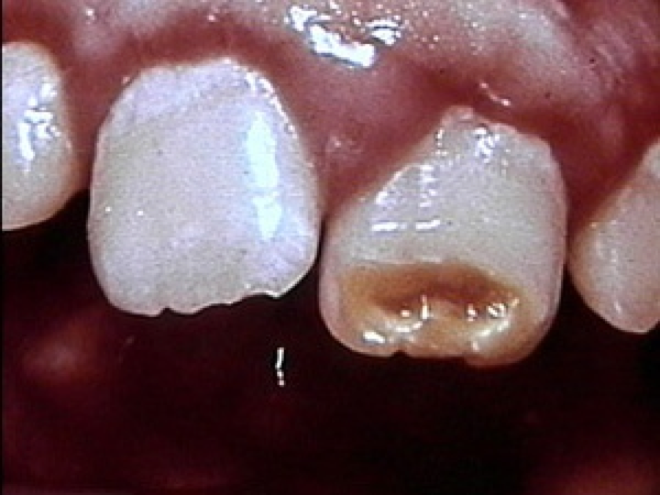

Anomalie de l’émail et de la dentine: dent de Turner:

Dent de tunner (qizlet.com).

Dent de Turner (qizlet.com).